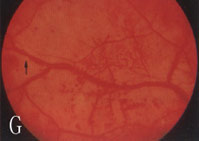

6、其他臟器併發症表現心血管病變如心力衰竭、心肌梗死。神經病變如周圍神經病變。累及自主神經時可出現神經源性膀胱。視網膜病變,糖尿病腎病嚴重時幾乎100%合併視網膜病變,但有嚴重視網膜病變者不一定有明顯的腎臟病變。當糖尿病腎病進展時,視網膜病變常加速惡化。

2.糖尿病視網膜病變和腎臟微血管病二者可同時存在。視網膜病變可繼發於糖尿病腎腎病以後,一般認為網膜病變的發生率高於腎微血管病變。因網膜病變易於觀察,而糖尿病腎腎病難於診斷,所以糖尿病人一旦出現網膜病變,要警惕腎病發生。